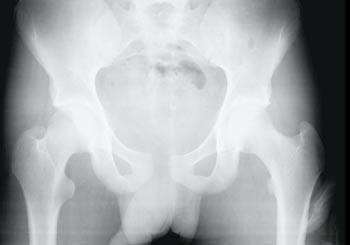

Pasient 4. En 16 år gammel gutt var passasjer på en mellomstor motorsykkel som kolliderte med en møtende motorsykkel. Begge førerne døde på stedet. Pasienten gikk selv med støtte til en bil ca. 50 meter fra skadestedet. Han lå i bilen, Glasgow Coma Scale var 14, blødde fra munnen og hadde en åpenbar ansiktsskade med kjevefraktur. Han var blek, kald på hendene, hadde puls 110 per minutt og frøs. Blodtrykket var 130 mm Hg. Han angav mest smerte i kjeven, men også nederst i magen. Han kunne bevege beina.

Bekkenet ble av luftambulanselege vurdert som stabilt. Han var antydet øm i nedre del av abdomen. I akuttmottaket var første måling av Hb 13 g/100 ml, pulsen 130 per minutt, og blodtrykket uendret.

Røntgen bekken tatt i akuttmottaket viste diastase i symfysen (fig 3) og CT-undersøkelse viste det samme, med ekstravasering av kontrast fra symfysen og retroperitonealt i bekkenet.

Over de neste seks timene falt hemoglobinkonsentrasjonen til om lag 7 g/100 ml og han trengte transfusjon. Pasienten hadde en a. iliaca-skade som ble radiologisk embolisert. Han overlevde, men endelig behandlingsresultat er ukjent.